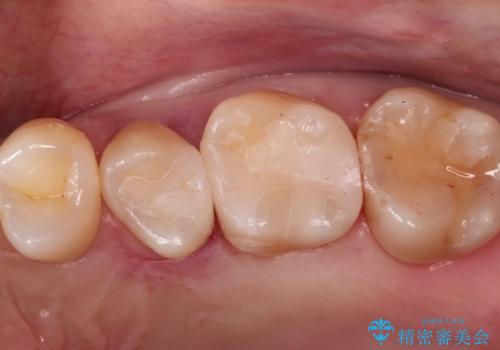

【メタルフリー】オールセラミッククラウン

- 金属冠を白くしたいことを主訴に来院されました。

オールセラミッククラウン(st)にて修復しております。

根管治療も合わせて行なっているため、期間がかかっております。